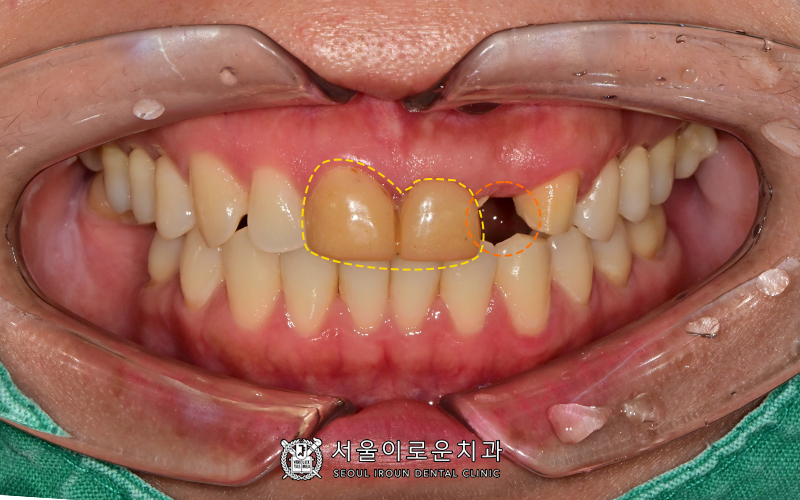

본원에 처음 오셨을 때의 구내 사진입니다.

“신장이식 때문에

대학병원에서 급하게

앞니 부분 임시치아 만들었어요.

임시치아가 부러져서

앞니 다시 하고 싶어요.”

환자분께서는 다음과 주소로 내원하셨는데요.

앞니 임시치아가 부분적으로 부러져 없고

치아 한 개는 결손된 상태셨습니다.

더불어 임시치아의 모양이나 색상이

부자연스러운 상태셨는데요.